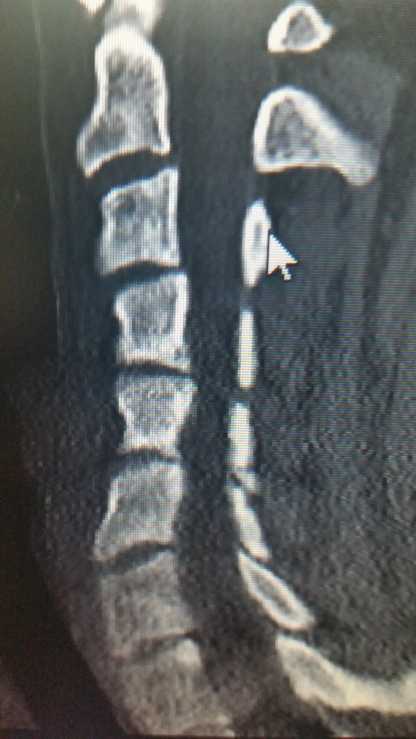

So today I saw my 'new' pain specialist. I say new but I've been a coworker of his for 3 years. He took one look at my cervical CT and shuddered. 3 neurosurgeons and a spinal surgeon and a different pain specialist ALL said my neck looked fine. ...

Posted by LadyAlyxandreaSo I finally have the date for MEETING my new neurosurgeon.